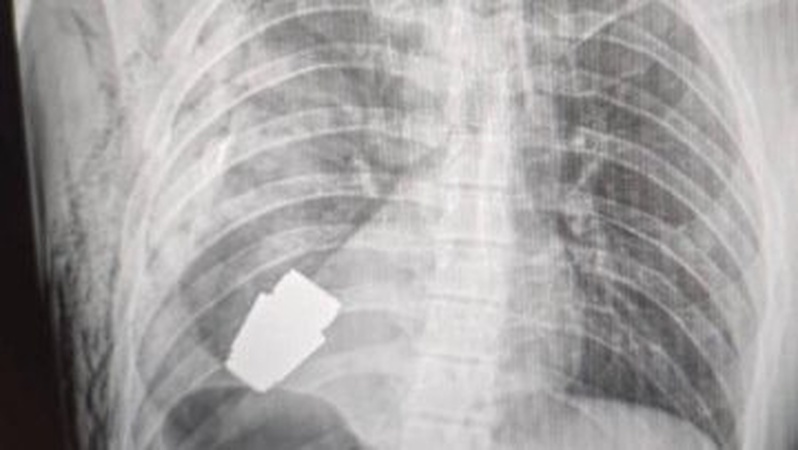

Військові лікарі провели операцію з видалення гранати ВОГ, яка не розірвалася, з тіла військовослужбовця.

Гранату видалили у присутності двох саперів, які страхували безпеку медичного персоналу.

"Операція проводилася одним з найдосвідченіших хірургів ЗСУ — Андрієм Вербою без електрокоагуляції, оскільки граната могла детонувати у будь-який момент", — розповіла Маляр.

Оперативне втручання пройшло успішно, а пораненого військовослужбовця відправили на подальшу реабілітацію та відновлення.